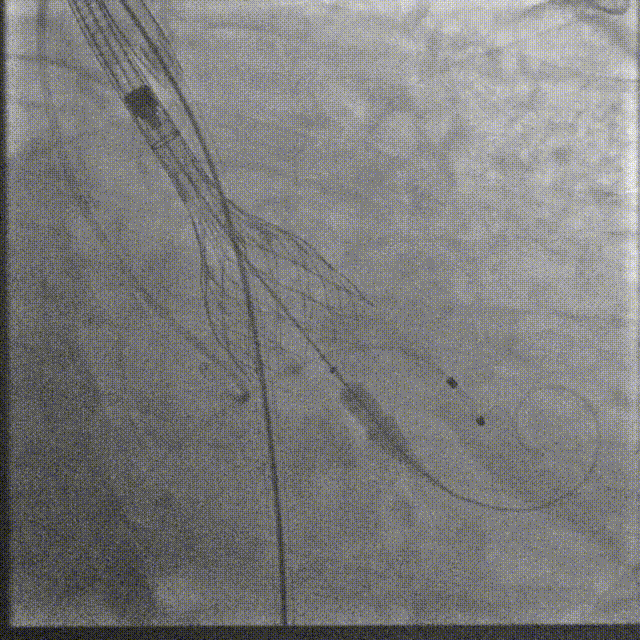

瓣膜系统过弓

定位造影

瓣膜确认位置后释放

回收极限处造影

最终造影

术后复查造影示瓣膜位置满意,形态良好,冠脉显影良好;TTE示轻微瓣周漏;排除入路血管问题,手术圆满成功。